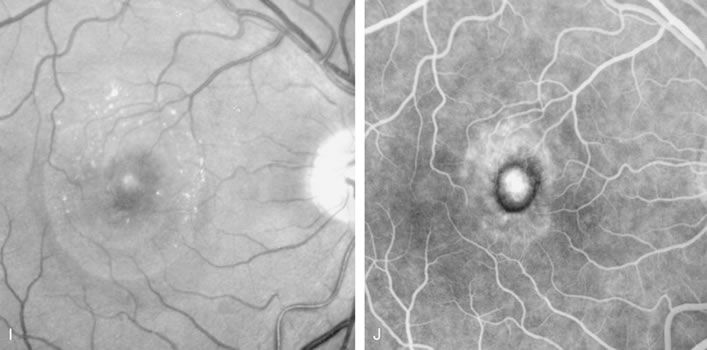

Fig. 20. A. Red-free photograph of a 20-year-old patient with sudden loss of vision to the level of 20/200. There is exudative, neurosensory macular detachment, a few hemorrhages, and lipid exudates. B. Fluorescein angiography reveals the presence of classic choroidal neovascularization (CNV), which appears to be juxtafoveal (<200 μ from fixation). Given the size of the CNV and its proximity to the fovea, it was decided to treat the patient with photodynamic treatment (PDT). C. Red-free photograph of the same eye 2 weeks after PDT; there is increased subretinal exudation D. Fluorescein angiography demonstrates that the CNV is still actively leaking. E. Red-free photograph 4 weeks after PDT demonstrates further increase in the size of the neurosensory macular detachment, subretinal hemorrhages, and lipid exudation. F. Fluorescin angiography reveals that the CNV has extended under the fovea. Given the young age of the patient, an inflammatory component of the neovascular process was suspected. It was decided to give a posterior, subtenon injection of triamcinolone acetonide, 40 mg/1 mL. G. Two weeks after steroid treatment there is partial reabsorption of the subretinal fluid. H. Fluorescein angiography demonstrates contraction of the CNV. I. Four weeks after injection of triamcinolone there is further reduction in the degree of neurosensory detachment; vision had improved to 20/60. J. Fluorescein angiography demonstrates that the CNV is smaller and less active (less leakage).